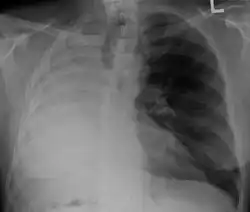

Pleural effusion

.jpg)

A pleural effusion is an accumulation of fluid inside the pleural space. If this collection of fluid gets large enough, it can also push structures in the chest away from it and cause a mediastinal shift. However, a pleural effusion can also pull the mediastinal structure towards itself. If this is the case, then there is an underlying condition causing the collapse of the lung on that side. An example is a tumor obstructing a bronchus and causing lung collapse and pleural effusion.[3]